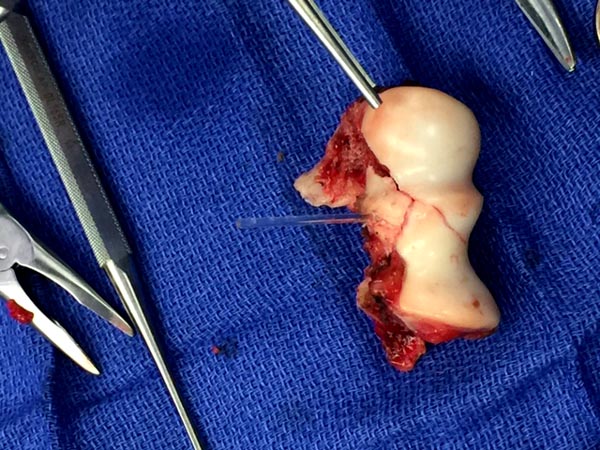

Но фрагмент очень большой, размером с надколенник.

Может все-таки попытаться фиксировать? Регенераторные способности у детей намного выше.

После травмы прошел месяц, отломавшийся фрагмент мертв. Чтобы убрать артроскопически, его можно фрагментировать на более мелкие куски. Функциональные результаты очень хорошие даже у лиц более старшего возраста.